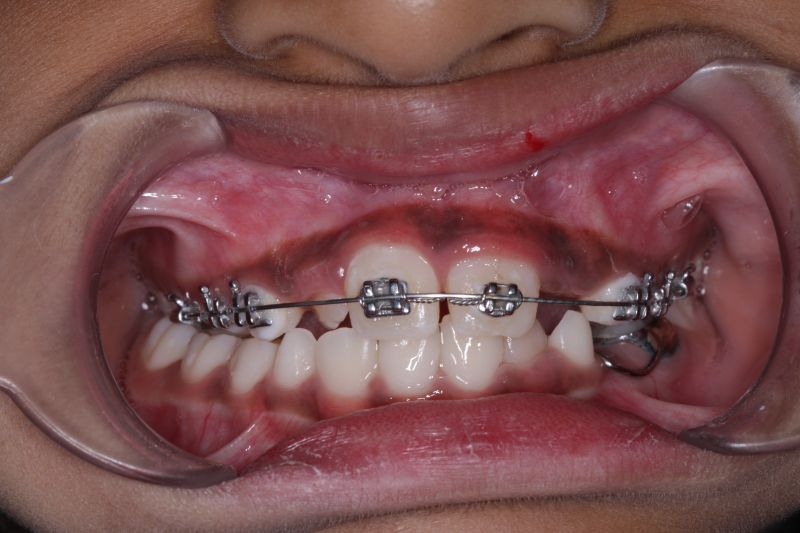

Early braces treatment correct the irregularly placed teeth and create room for erupting permanent teeth. correct bite problems such as open bite, cross bite and improves the appearance and self esteem of the child.